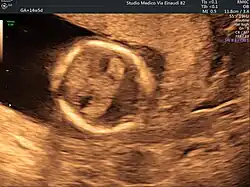

Ultrasound scan of a fetal head at 14 weeks of pregnancy with partial absence of the midline

Holoprosencephaly is typically diagnosed during fetal development when there are abnormalities found on fetal brain imaging, but it can also be diagnosed after birth. The protocol for diagnosis includes neuroimaging (Ultrasound or fetal MRI prior to birth or Ultrasound, MRI or CT post birth), syndrome evaluation, cytogenetics, molecular testing, and genetic counseling.[3]